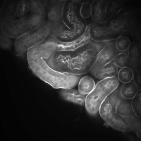

Our proposed method uses this inhomogeneity correction technique as a preprocessing step for both training and inference. Examples of original and inhomogeneity corrected images are shown in Figure 3a and Figure 3b, respectively.

The performance of our proposed method was tested on two different datasets:111 and were provided by Malgorzata Kamocka of the Indiana Center for Biological Microscopy. and . is comprised of grayscale images, each of size pixels, whereas consists of grayscale images, each of size pixels. We selected five different images from and generated corresponding manually annotated groundtruth images to train model . Our deep learning architecture was implemented in Torch [31] using a fixed learning rate and a momentum of . As indicated, pairs of images were generated by the elastic deformation, rotations, and flips using these five pairs of images. Note that each training data was used as a batch so that iterations were performed per epoch. We used epochs for training our proposed network. In addition, was used for the removal of small objects. The performance of the proposed method was evaluated using manually annotated groundtruth images () at different depths in that were never used during the training stage. For visual evaluation and comparison segmentation results of in using various techniques are presented in Figure 3.

The first row in Figure 3 displays an original microscopy image (), its inhomogeneity corrected version (), and manually delineated groundtruth (), respectively. For brevity we have omitted the superscript in the notation. The second row shows segmentation results of various 3D methods such as 3D region-based active contours [10] (3Dac), 3D active contours with inhomogeneity correction [11] (3DacIC), and 3D Squassh presented in [12] (3Dsquassh). Similarly, the third row portrays various segmentation methods particularly designed for tubular structure segmentation such as ellipse fitting method presented in [15] (Ellipse Fitting), the Jelly filling method in [20] (Jelly Filling), and tubule segmentation using steerable filter [21] (Steerable Filter). Finally, the last row shows segmentation results of our proposed CNN architecture without inhomogeneity correction [27] (2DCNN) and with inhomogeneity correction (2DCNNIC).

For visual evaluation we provide the segmentation results of the proposed method using two different datasets: and , sampled at different depths within the volumes. The first row shows original microscopy images , , and from and the second row displays the segmentation results corresponding to the first row. To better visualize the segmentation results, we highlighted individual tubules with different colors and overlaid them onto the original microscopy images. Similarly, the third row exhibits original microscopy images , , and from . Their corresponding segmentation results are shown in the fourth row. Note that the model which was trained on was used for during the inference stage. Although the shape, size, and orientation of tubular structures presented in are all different from , the proposed method can still successfully segment and identify individual tubules presented in as well as individual tubules in .